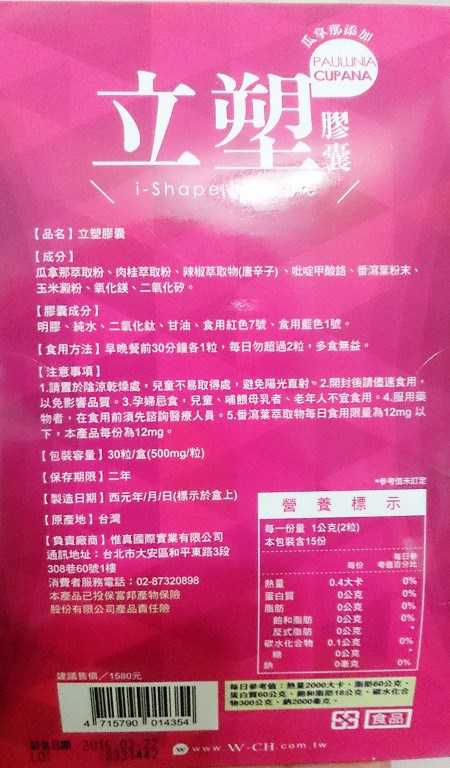

Supercut塑魔纖立塑膠囊的成分有:瓜拿那萃取粉、肉桂萃取粉、辣椒萃取物(唐辛子)、吡啶甲酸鉻、番瀉葉粉末、玉米澱粉、氧化鎂、二氧化矽。

之前上過相關課程,成分表是依照每項成分的多寡來排列順序,排在最前面的就是產品的主要成分!

食用方式:早晚餐前30分鐘各1粒,每日不超過2粒。(多食無益)

番瀉葉萃取物每日食用限量為12mg以下,

番瀉葉萃取物每日食用限量為12mg以下,